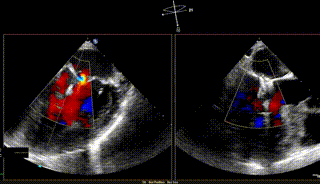

【二尖瓣相关参数】二尖瓣重度反流(继发性:Carpentier II型);A3:21mm P3:13mm,MVOA:5.3cm²,P3脱垂连枷,3区病变,瓣叶质地欠佳。

术前反流

在MultiVue下定位与夹合

反流基本消失